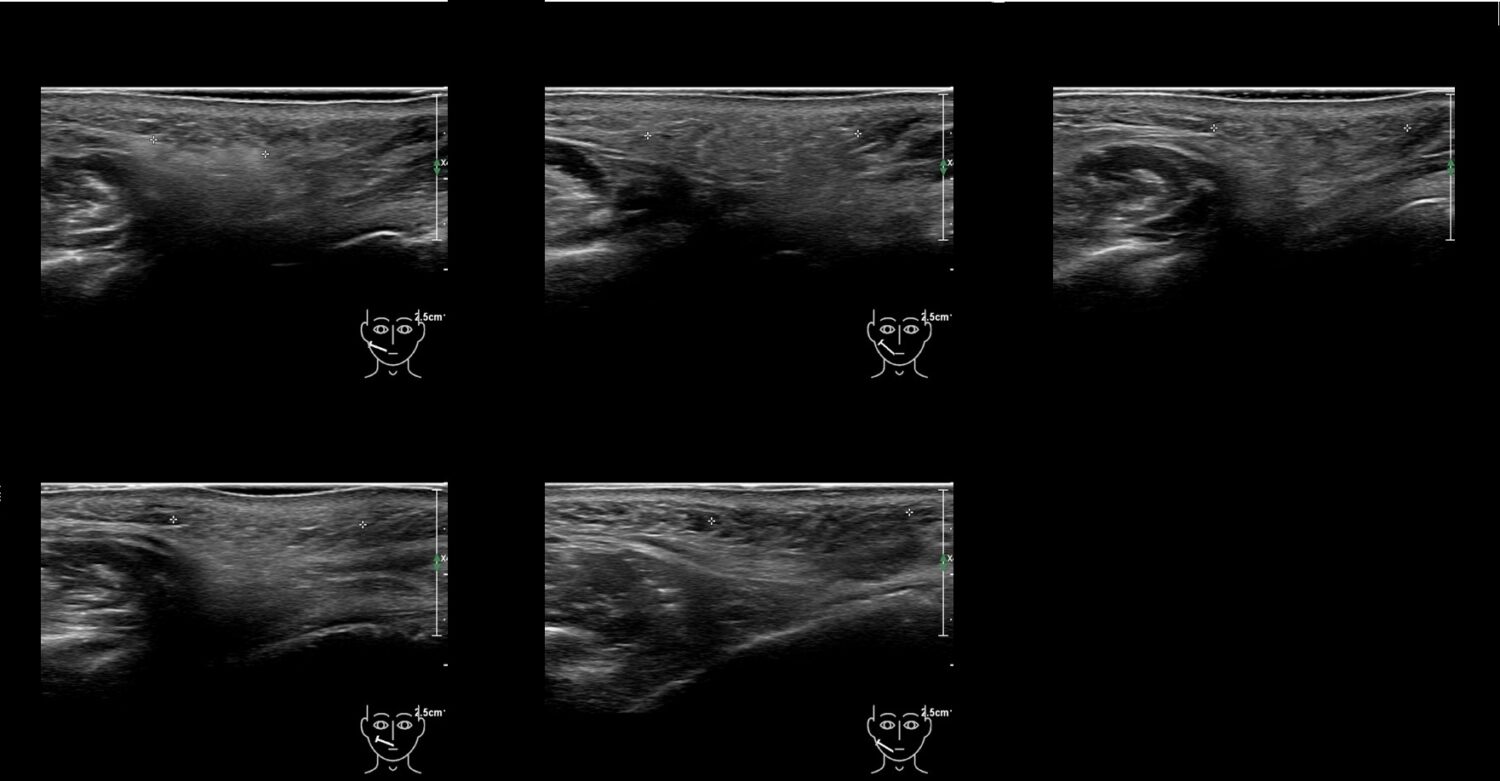

Fillers

Draw in the second image below where the fillers are located. To check if your answer is correct, swipe the first image to the right.